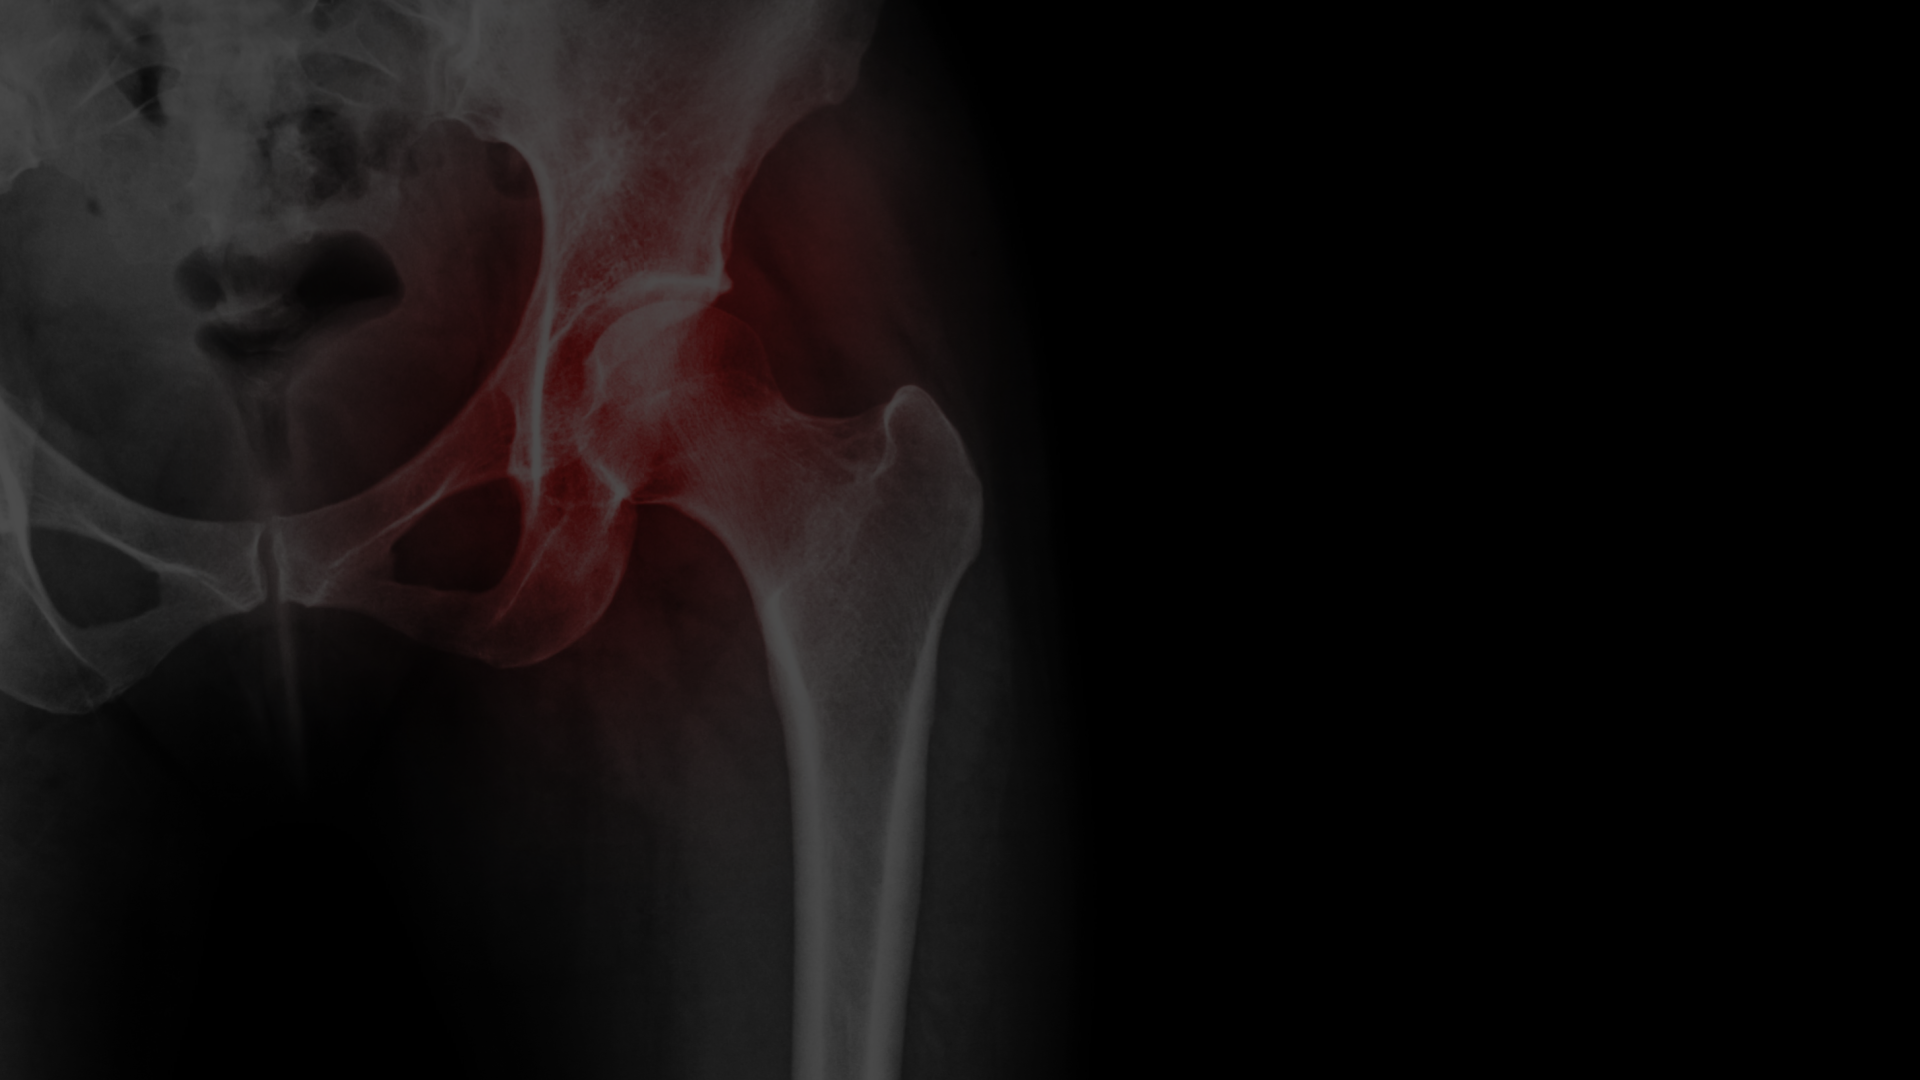

Extensive Experience in Hip Surgery

Mr Islam uses the most modern techniques within his surgeries. He is the hip fracture lead in Liverpool University Hospitals and is an active part of the Liverpool Metastatic bone tumour service and revision arthroplasty multidisciplinary team.Below you'll find a range of different surgeries available and the process we created to keep all our clients happy and healthy.

We provide comprehensive treatment for hip fractures and other traumatic injuries affecting the hip joint. Mr Saif uses advanced techniques to stabilise fractures and repair damaged tissue.

We offer surgical and nonsurgical treatments for avascular necrosis of the hip. Our goal is to intervene early to prevent collapse and preserve the hip joint.

We help patients find relief from hip pain. Treatment options range from medication and injections to minimally invasive joint preservation procedures and joint replacement surgery.